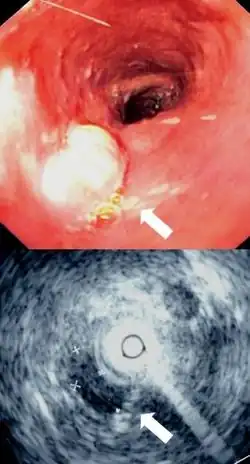

L'esofago può essere affetto dalla malattia da reflusso gastroesofageo, dal cancro, da prominenti dilatazione dei vasi sanguigni chiamati varici che possono sanguinare gravemente, costrizioni e disturbi della motilità. Le malattie possono causare difficoltà di deglutizione (disfagia), deglutizione dolorosa (odinofagia), dolore al torace o essere asintomatiche. Le indagini cliniche includono la radiografia in seguito alla deglutizione di bario, l'endoscopia e la tomografia computerizzata.

Tecniche diagnostiche

Una radiografia effettuata dopo aver ingerito bario come mezzo di contrasto, può essere utilizzata per rivelare la dimensione e la forma dell'esofago, oltre alla presenza di eventuali masse. L'esofago può anche essere ripreso con una telecamera flessibile inserita in esso, in una procedura chiamata "endoscopia". Nel corso di una endoscopia, può essere effettuata una biopsia sul tessuto. Se viene sospettato un tumore dell'esofago, si può fare ricorso ad altre tercniche di imaging biomedico più avanzate, tra cui la tomografia computerizzata e la tomografia a emissione di positroni.[3]